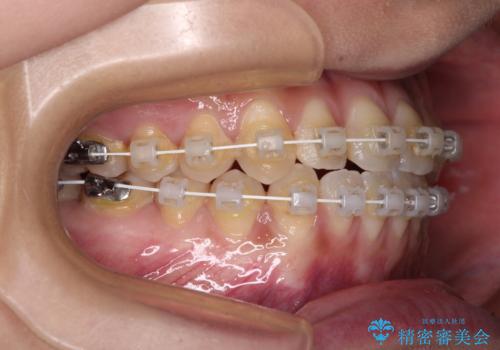

- 審美装置

- 治療期間

- 2年

クロスバイト改善まではスムーズに進みましたが、その後は強い舌の突出癖によりオープンバイトの期間が長く続きました。

舌のトレーニングをしっかりと実施してもらい、何とか仕上げることができました。